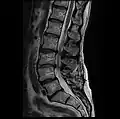

MRI lumbar spine pre-hemilaminectomy (sagittal T2 FRFSE)

-

MRI lumbar spine pre-hemilaminectomy (sagittal T1 FSE)

MRI lumbar spine pre-hemilaminectomy (sagittal FAST STIR)